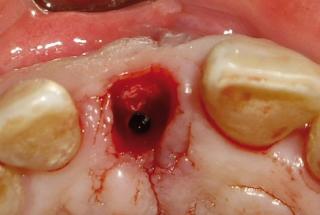

Clinical cases

MPI closely monitors clinical cases in the market to ensure their correct functioning and successful outcome.